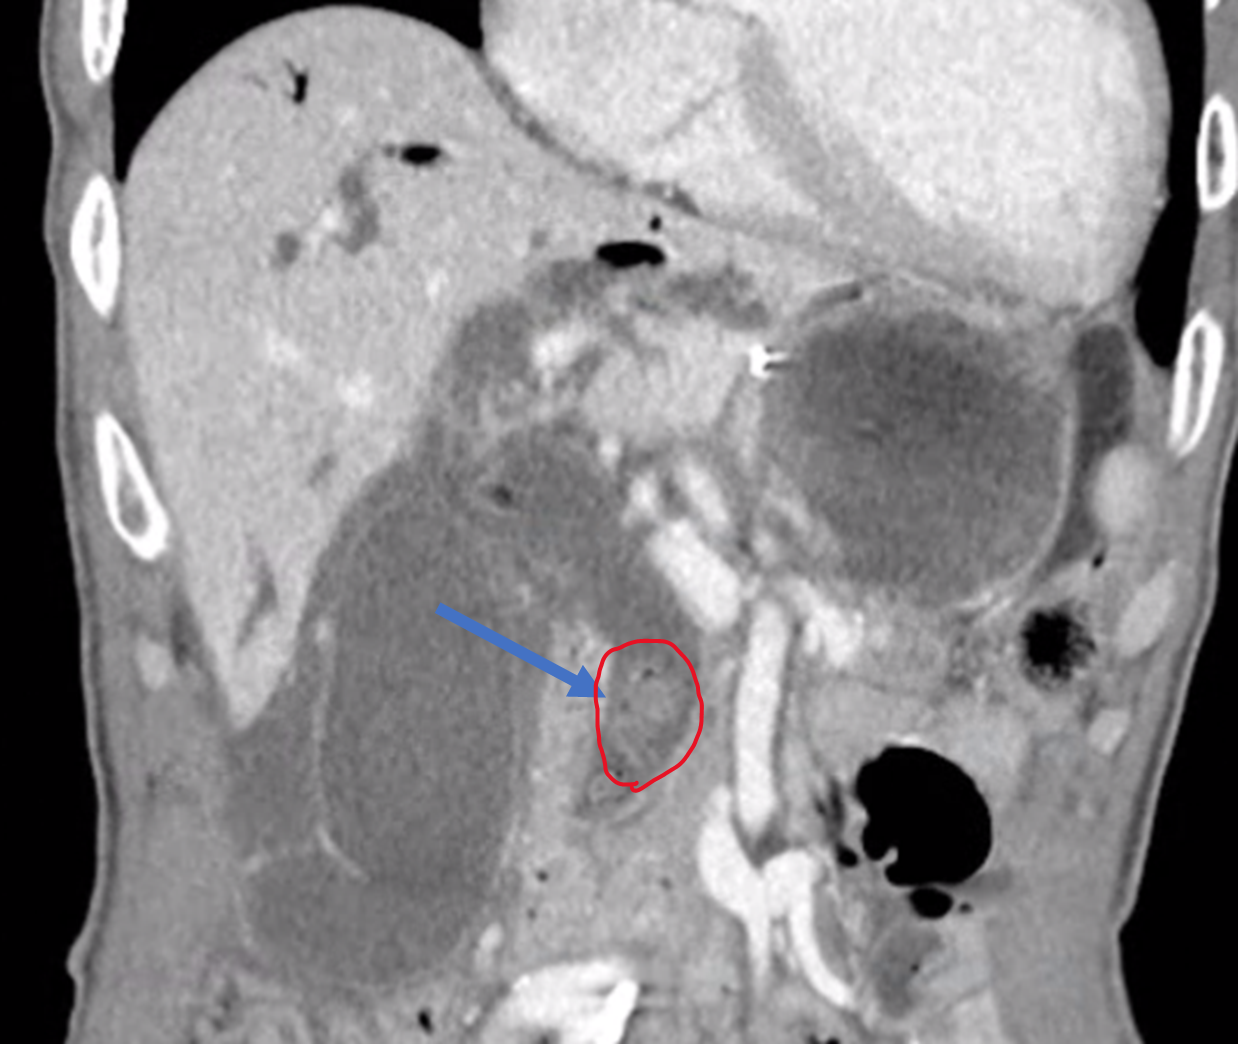

먼저 CT를 촬영해야 하고요.

CT 촬영에서 이 환자에게 이 시술이 정말 필요한 상황인지, 시술 자체에 어려움이나 합병증을 유발할 만한 다른 요인은 없는 지 확인합니다.

다음으로 혈관조영실로 환자분을 이송 시킨 뒤

초음파로 늘어난 간내담관을 확인합니다.

위에 제가 올린 CT 처럼 간내담관이 아주 늘어난 경우에는 초음파로도 담관이 잘 보입니다.